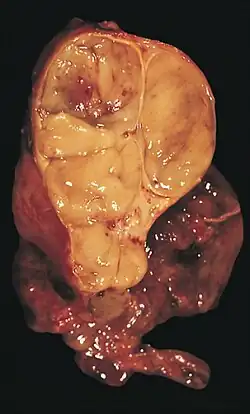

An encapsulated thymoma (mixed lymphocytic and epithelial type)